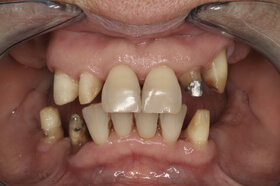

Több, mint tízéves koronák és az íny visszahúzódása a frontfogak ajak felőli oldalán

Felső négy frontfog korona cseréje és az íny visszahúzódásának korrekciója a szájpadból vett kötőszöveti lebennyel

Felső és alsó sorvégi foghiányok

A foghiányok ellátása fém-kerámia koronákkal és az ezekhez kapcsolódó részleges kivehető fogpótlásokkal

A négy felső frontfog helyén hídpótlás a hiányzó jobb felső nagymetsző miatt. A foghiány miatt az íny negatív kontúrja figyelhető meg

A negatív ínykontúr korrekciója a szájpadból vett kötőszöveti lebennyel és az ideiglenes fogpótlással

Az új híd hat héttel az ínyműtét után készült el

Több, mint tízéves hidak, elkopott fogak. Kezelési terv: a régi hidak cseréje és a többi fog ellátása fém-kerámia koronákkal

Az elkészült fém-kerámia koronák, hidak